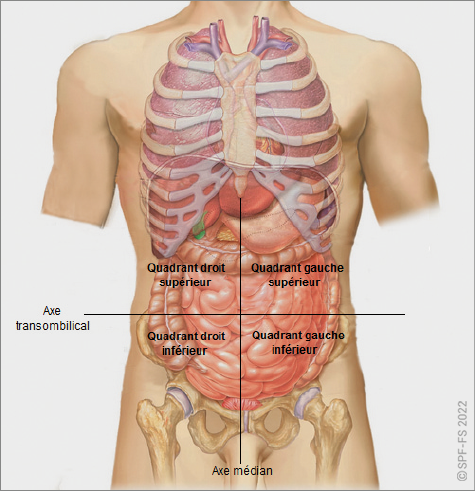

Le corps est divisé en plusieurs parties, elles-mêmes subdivisées en régions (cf. Figure 2-3) :

Figure 2-3 : les différentes parties et régions du corps humain